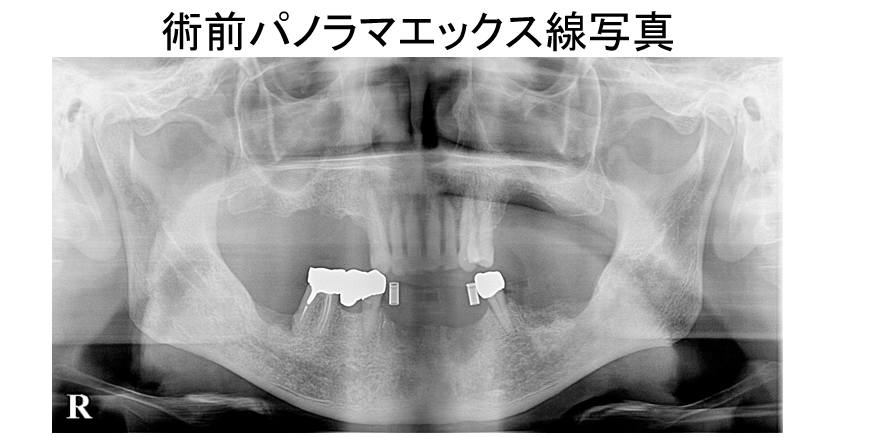

下顎右側3から左側7までの10歯欠損症例。ボーンアンカードブリッジによる治療を行いました。

インプラント治療の必需品、CT。デジタルワックスアップと重ね合わせをして、埋入ポジションや使用するインプラント体の長さや径を決定します。